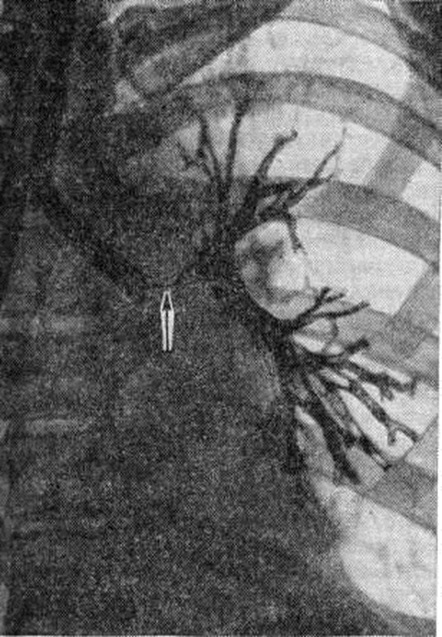

Диагноз диссеминированного туберкулёза лёгких ставят на основании бактериологического, иммунологического, бронхологического, а также микроскопического исследования материала, полученного с помощью пункционной биопсии. Однако ведущая роль в распознавании этой формы туберкулёза лёгких принадлежит рентгенологическое методу исследования. На основании рентгенологическое данных выделяют различные типы диссеминированного процесса. Острый диссеминированный туберкулёз характеризуется наличием в лёгких множественных очагов. В зависимости от их размеров выделяют мелкоочаговый (милиарный), среднеочаговый и крупноочаговый типы диссеминации.

При мелкоочаговом типе диссеминации размеры очагов не превышают 3 миллиметров в диаметре, очаги имеют однотипный характер, ясные очертания и равномерно рассеяны по обоим лёгочным полям. Очаги образуют комплексные тени с инфильтративно-уплотнённой интерстициальной тканью; структура лёгких при этом приобретает мелкосетчатый, петлистый характер; сосудистый рисунок не прослеживается (рисунок 5).

Рис. 5.

Рентгенограмма грудной клетки при милиарном туберкулёзе (прямая проекция): видны множественные тени во всех отделах лёгких, образованные мелкими очагами и инфильтративными интерстициальными изменениями; сосудистый лёгочный рисунок не определяется.